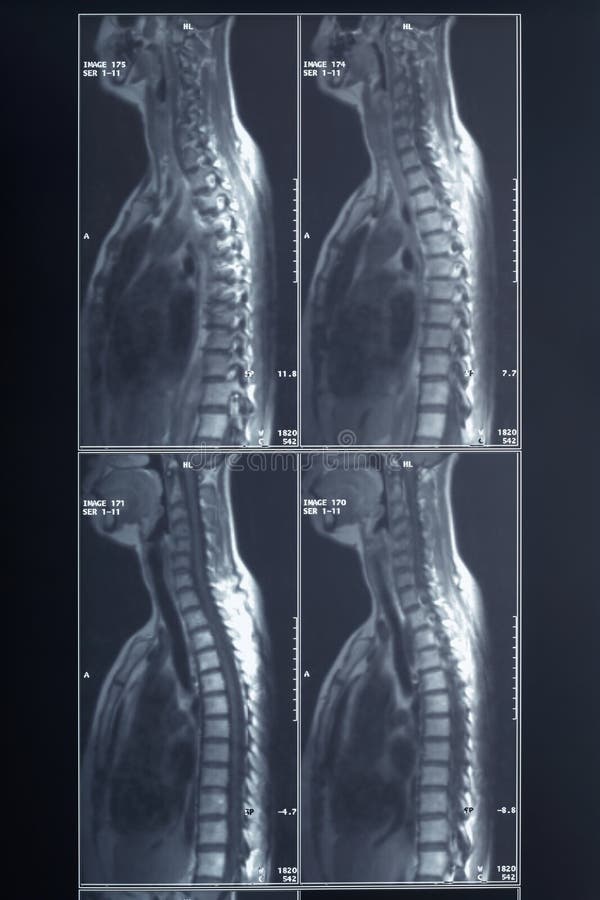

Radiografia Della Colonna Vertebrale Rmi Del Collo E Testa Di Stress Fotografie Stock E Altre Immagini Di Adulto Istock

Immagini Stock Radiografia Del Collo E Del Rachide Cervicale Test Funzionale Laterale Lat Instabilita Image

Radiografia Della Colonna Vertebrale Rmi Del Collo E Testa Di Stress Fotografie Stock E Altre Immagini Di Collo Umano Istock